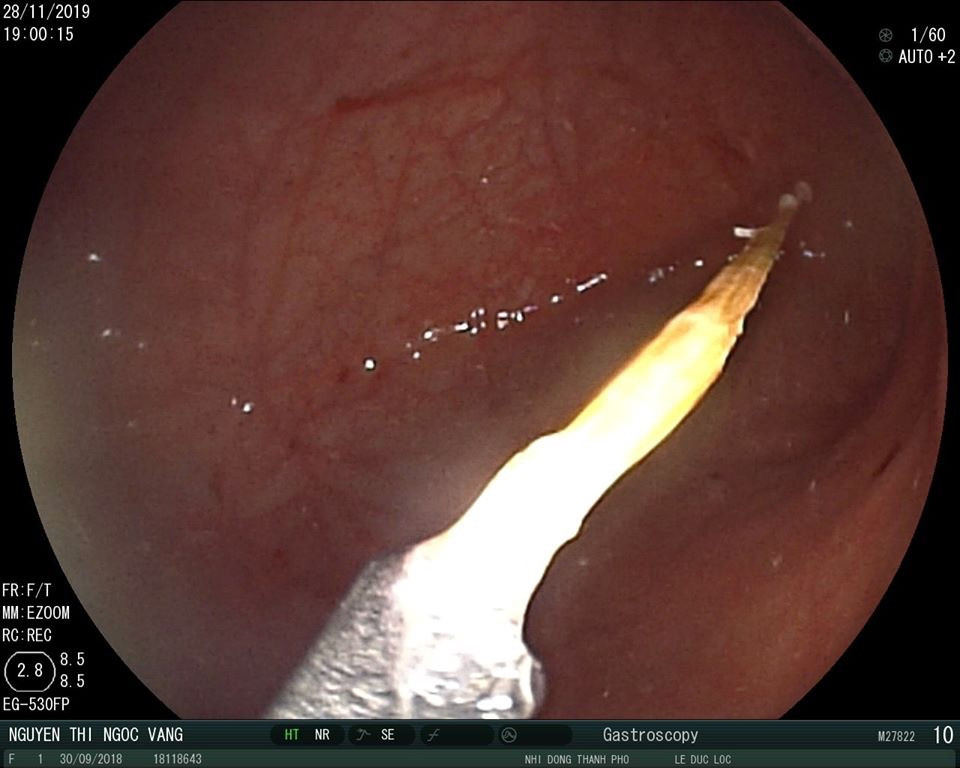

Hình ảnh dị vật khi tiến hành nội soi.

Bác sĩ Lộc thận trọng xác định đúng vị trí chiếc tăm để đưa ra ngoài, tránh làm tổn thương niêm mạc dạ dày cũng như ruột của bệnh nhi. "Rất may là cây tăm nằm dọc thuận chiều, nên các BS đã dùng kiềm gắp dị vật  ra ngoài. Lúc được nội soi,  cây tăm đã di chuyển tới hành tá tràng, nếu gắp dị vật trễ, cây tăm trôi qua khỏi tá tràng thì nguy cơ thủng ruột rất lớn. Hiện tại, sức khỏe bệnh nhi ổn định và có thể được xuất viện trong nay mai", bác sĩ Lộc cho biết